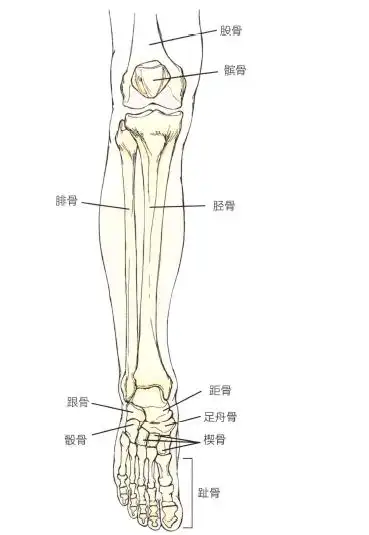

人正常小腿骨图

在这里我详细科普一下,你看,每个人都有两根小腿骨,一根粗一点的叫

人体的小腿内,主要有两根长骨组成,较粗壮的称为胫骨,起着主要的支撑

胫骨位于小腿内侧,对支持体重有重要的作用.也分为两端和一体.